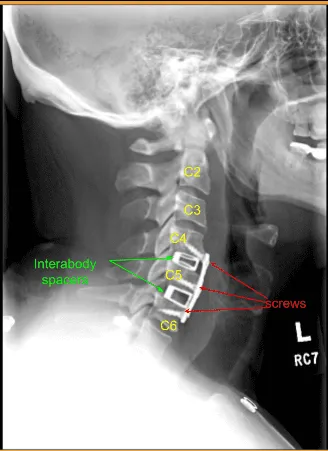

At this point we measured out our anterior plate, placed it over our levels of interest, and pinned it into place. We obtained x-rays, and then removed the plate and applied additional curvature to the plate to seat it appropriately against the anterior border of the vertebral bodies. We then replaced the plate and applied the screws as listed above. We locked all the screws in place and obtained final AP and lateral x-rays.